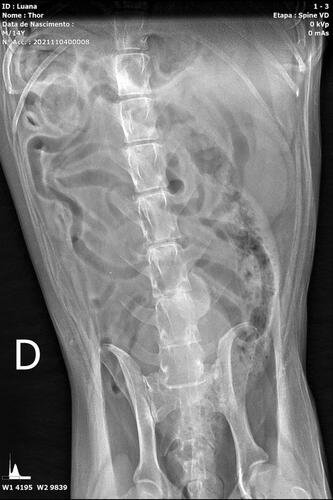

Thor é um senhorzinho que sofre com a síndrome da cauda equina, que é uma doença grave causada pela compressão e inflamação do feixe de nervos na parte inferior do canal vertebral. A gravidade se dá ao fato de poder resultar em paralisia, incontinência intestinal / urinária e a outros problemas de sensibilidade e perda de movimento.

Thor já apresenta todos os sintomas e precisa passar por procedimentos veterinários, necessita de fisioterapia para estimular o retorno do controle esfincteriano (válvula urinária e fecal) e medicações. Uma cirurgia também pode ser o caminho de acordo com o neurologista veterinário.